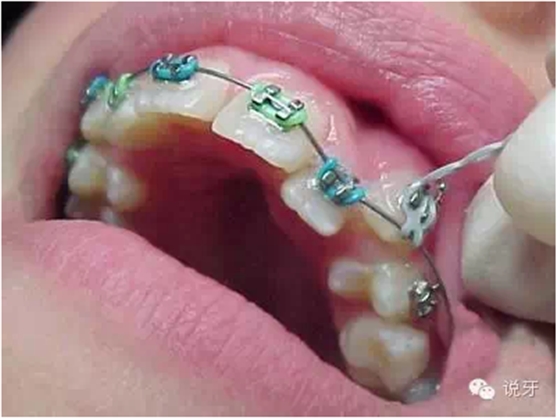

7、上牙套

最忐忑的時候到了。剛開始戴上牙套會有點不適感,有些可能還引發(fā)口腔潰瘍,牙齒也會有些酸痛感,這種狀況一般持續(xù)一周左右。戴上牙套后不宜吃有粘性、硬度大的食物。

9、上橡皮筋

一般來說,牙齒的排齊會因本身的牙齒移動快慢和醫(yī)生的技術(shù)各方面因素而不同。一般1個月左右能顯現(xiàn)出一些變化,而6個月左右基本排齊。牙齒排齊以后牙縫開始收合,此時需要皮筋的幫忙。需要注意的是皮筋在吃飯時需要摘下來。